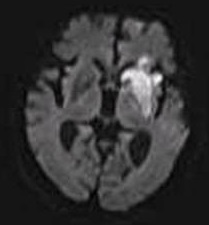

Diffusion Weighted Imaging (DWI)

Motion of water molecules

White Matter Pathways

Approximation!